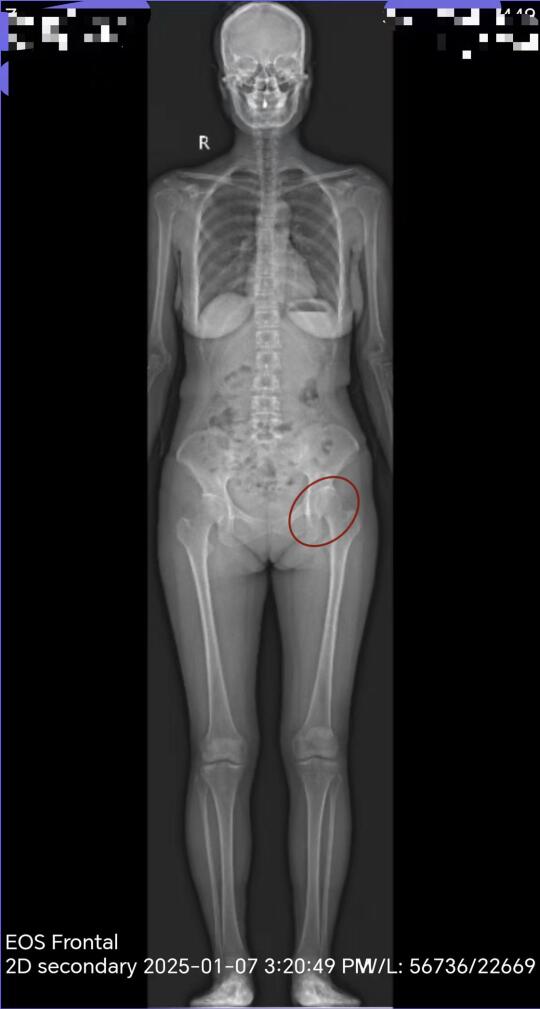

导致骨盆失衡案例 案主来自广州 年前与我联系帮她在线分析片子 先后在广州找过多个康复室甚至也有看诊礒谷力学疗法 我说我研究骨盆与股关节的问题也是在礒谷力学的基础上融汇了很多方法才形成自己独特的体系 从片子二可以看出左侧股骨头覆盖率比较小 股骨头顶在髋臼的前上方为为旋内转位并且在这个位置卡死了,这样就导致股骨头在髋臼内的内旋空间不足,骶髂关节的关节面前面紧而后面咬合不住,这样才导致她经常会觉得左侧腰不舒服。 触诊非常明显可以摸出左侧股骨头顶出髋臼比较多,所以她就会觉得左腿长而右腿短,站着的时候左侧大转子顶出来比较多,另外左侧股骨头向与髋臼的接触点明显比右侧高,这一点也可以判断出来 另外两侧髂骨都有外扩,与后倾,有明显臀部凹陷 耻骨联合距离比较宽 并且耻骨位置比较低 裤子总觉得卡裆 左侧腹股沟比较紧耻骨到股骨那里有筋牵扯 身体整个前伸链向下拉,没有力 通过两种负重训练来让骶髂关节咬合 案主95斤最后负重达到160斤,她自己说简直不敢想象,通过几组负重训练,腰大肌与髂肌很明显有力了,骨盆有向上的力了,内收肌也可以发力了。整个上半身挺拔了,前伸链觉得是可以发上力了。第二种负重训练了内收肌与膕绳肌,训练结束后感觉原来坐骨与耻骨向下丢的感觉弱了。并且耻骨联合距离近了,腹部的张力也大了,核心可以发力了。 其实关节开发负重训练非常重要,更重要的是结合关节的角度,力度与角度结合在一起,可以创造奇迹。